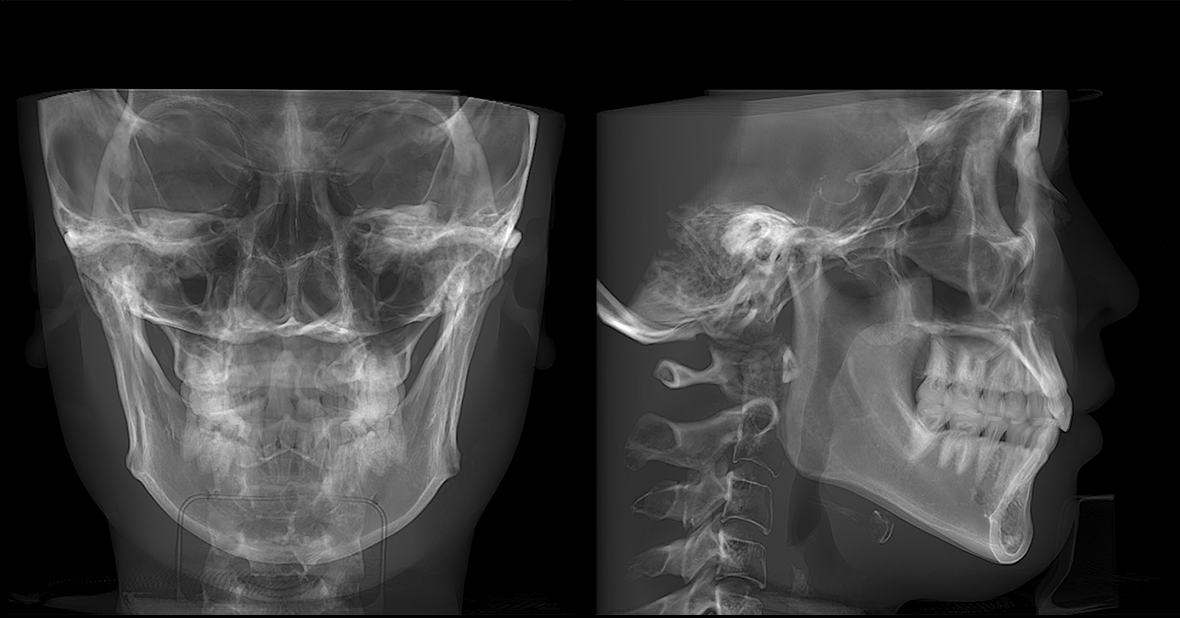

• lamtau AI頭影測量

AI頭影測量

單側頭影測量 專利 首創

偏頜患者的側位片左右側的影像不對稱,實際正畸測量時會產生較大的誤差。有方醫療推出單側頭影測量功能。這一功能有效解決了這一臨床問題,在口腔正畸領域廣受好評,并于2023年成功獲得國家發明專利授權。

單側頭影測量